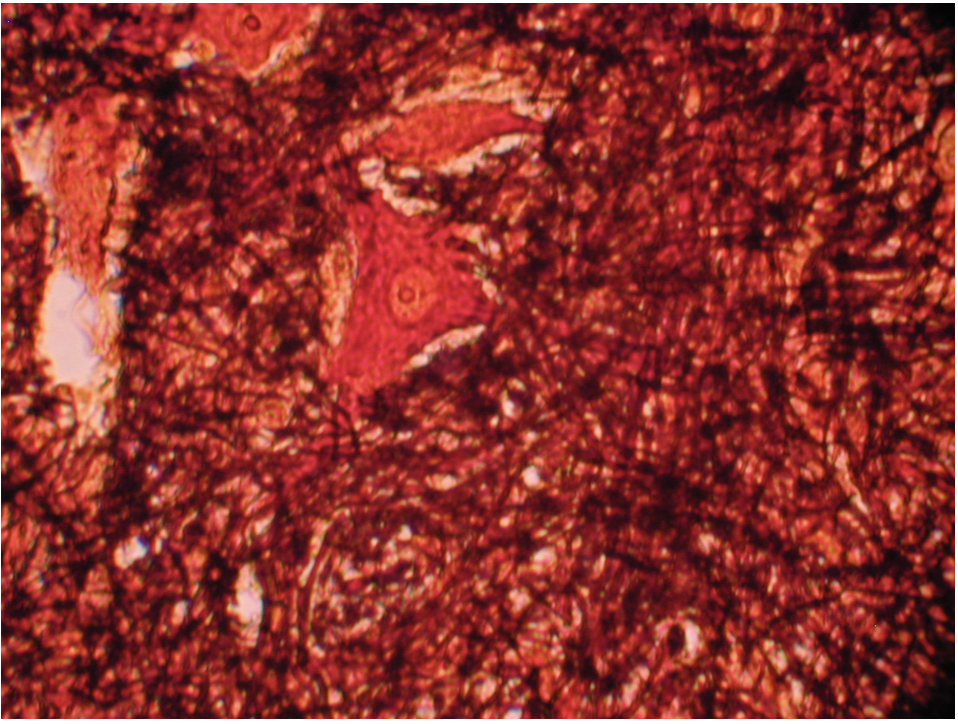

Nervous Tissue